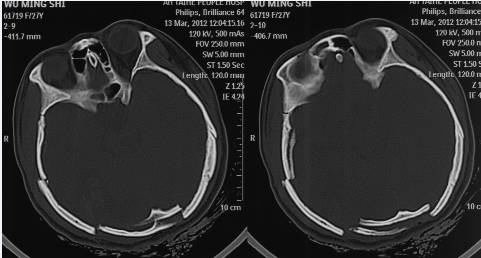

摄片显示,小娟颅骨多处粉碎性骨折, 颅内出血。“脑部受到较大的暴力作用,致重型颅脑损伤,小娟伤后应该是处于一个意识模糊状态甚至昏迷,这是她无法呼救的原因。”医院的病历报告也证实了王飞翔的猜测,上面清楚地记载着,患者就医时神志不清、呼吸不畅,大小便失禁。

颅脑CT

而关于双目失明的问题,记者也颇感好奇:受伤的是后脑,怎么眼睛就失明了呢?王飞翔说,当时他们也无法确定,于是就找了法医临床室副主任法医师、眼科鉴定方面的专家刘瑞珏,又去请来了神经外科的专家一同会诊。

结论是

小娟脑后受到打击造成枕骨粉碎性骨折,导致枕叶受损,枕叶受损又直接导致双眼失明。